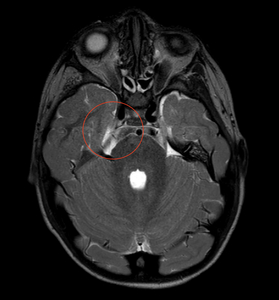

Despite no diagnosed genetic syndrome, we believe our patient has type II congenital trigeminal anesthesia given his significant medical history of septo-optic dysplasia with associated growth hormone deficiency and central hypothyroidism, global developmental delays with hypotonia, autism spectrum disorder, and sensorineural hearing loss. Magnetic resonance imaging of the brain and orbits performed when the child was aged 1 month revealed posterior pituitary ectopia, subependymal gray matter heterotopia, and left occipital subcortical gray matter heterotopia with overlying polymicrogyria, multiple cranial nerve abnormalities including bilateral optic nerve hypoplasia, a hypoplastic right trigeminal nerve, and small cochlear nerves (Figure 4). Repeat neuroimaging was performed at 4 years and 2 months of age (Figure 5) demonstrating stability of the septo-optic dysplasia and hypoplastic right trigeminal nerve.